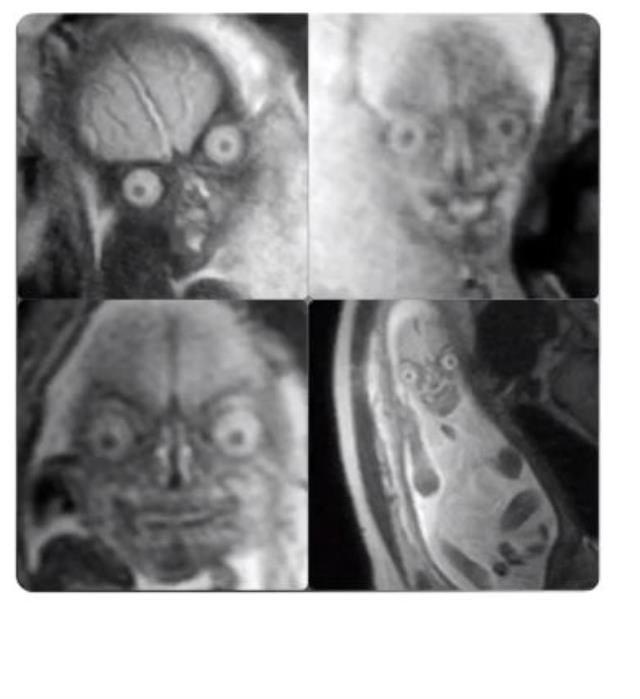

Anne karnındaki bir bebeğin ultrason görüntüsü, ilk kez görenleri bir hayli ürküttü. Söz konusu görüntünün ultrason ışıklarından kaynaklı ortaya çıktığı belirtildi.

Anne karnındaki bir bebeğe ait olduğu belirtilen ultrason görüntüsü, sosyal medyada kısa süre içerisinde çok sayıda yorum aldı.

Bebeğin ultrason görüntülerini ilk kez görenler bir hayli ürkerken, daha önce görenler ise korku yaşamadı. Fakat bebeğin gözlerindeki ürkütücülük çok sayıda kullanıcının dikkatini çekti.

Ultrason görüntüsündeki ürkütücülüğün ışıklardan kaynaklı olduğu ve deri altının da görünmesi nedeniyle böyle bir görüntü ortaya çıktığı belirtildi.

İşte bebeğin o görüntüsü: